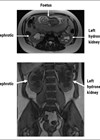

A duplex ureter, or duplex collecting system, is a congenital anomaly resulting from incomplete fusion of the ureteric buds during embryogenesis. It is one of the most common renal anomalies, occurring in approximately 0.8% of the population [1]. The Meyer-Weigert rule provides a predictable pattern for the insertion of duplex ureters into the bladder: the upper pole ureter drains the lower renal moiety and inserts inferomedially, while the lower pole ureter drains the upper renal moiety and inserts superolaterally [2]. This anatomical arrangement is critical for understanding the clinical presentation and management of duplex systems (Figure 1).

Figure 1: An anatomical drawing of complete unilateral duplication of the right ureter with ectopic orifice into the prostatic urethra. LU - lower ureter, UU - upper ureter, B – urinary bladder. CC BY 4.0 reproduced from: Balawender K, Wawrzyniak A, Pliszka A, et al [11].